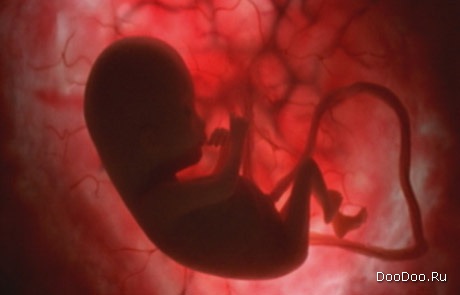

Ребенок теперь способен к движениям рук и пальцев. Может потереть щечку и носик. И силует ребенка виден немного лучше.